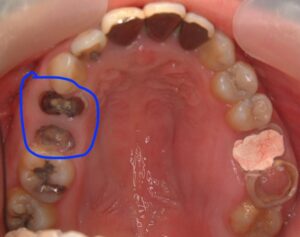

青○の部分が虫歯が進行して根っこだけになっています。